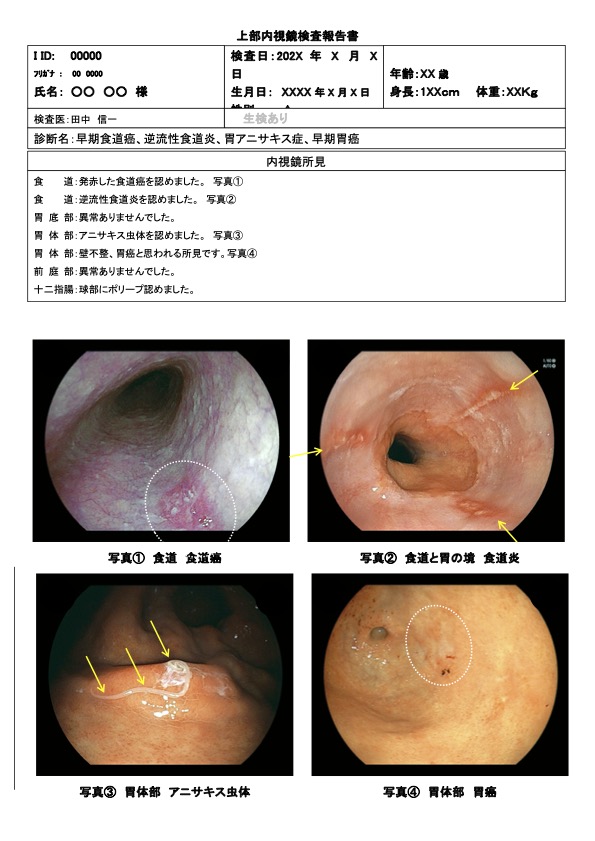

内視鏡検査の所見例

発赤した食道癌

内視鏡検査の所見例

発赤した食道癌